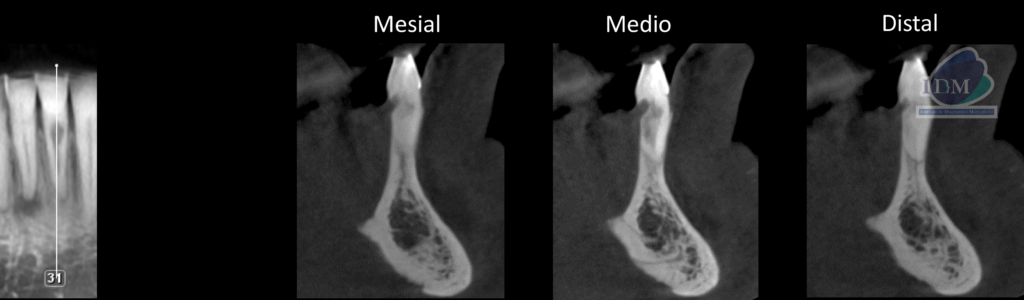

A la evaluación de la tomografía computarizada cone beam de campo mediano se observa en los cortes axiales, transaxialres y tangenciales la presencia de una imagen hipodensa que se localiza a nivel de tercio cervical de la pieza 31 por debajo del límite amelocementario en la superficie lingual la cual se comunica con el conducto pulpar ocasionando la alteración en su morfología, finalmente se observa un discreto ensanchamiento del espacio para el ligamento periodontal apical, compatible con reabsorción cervical invasiva (RCI)

CORTES TANGENCIALES

CORTES TRANSAXIALES